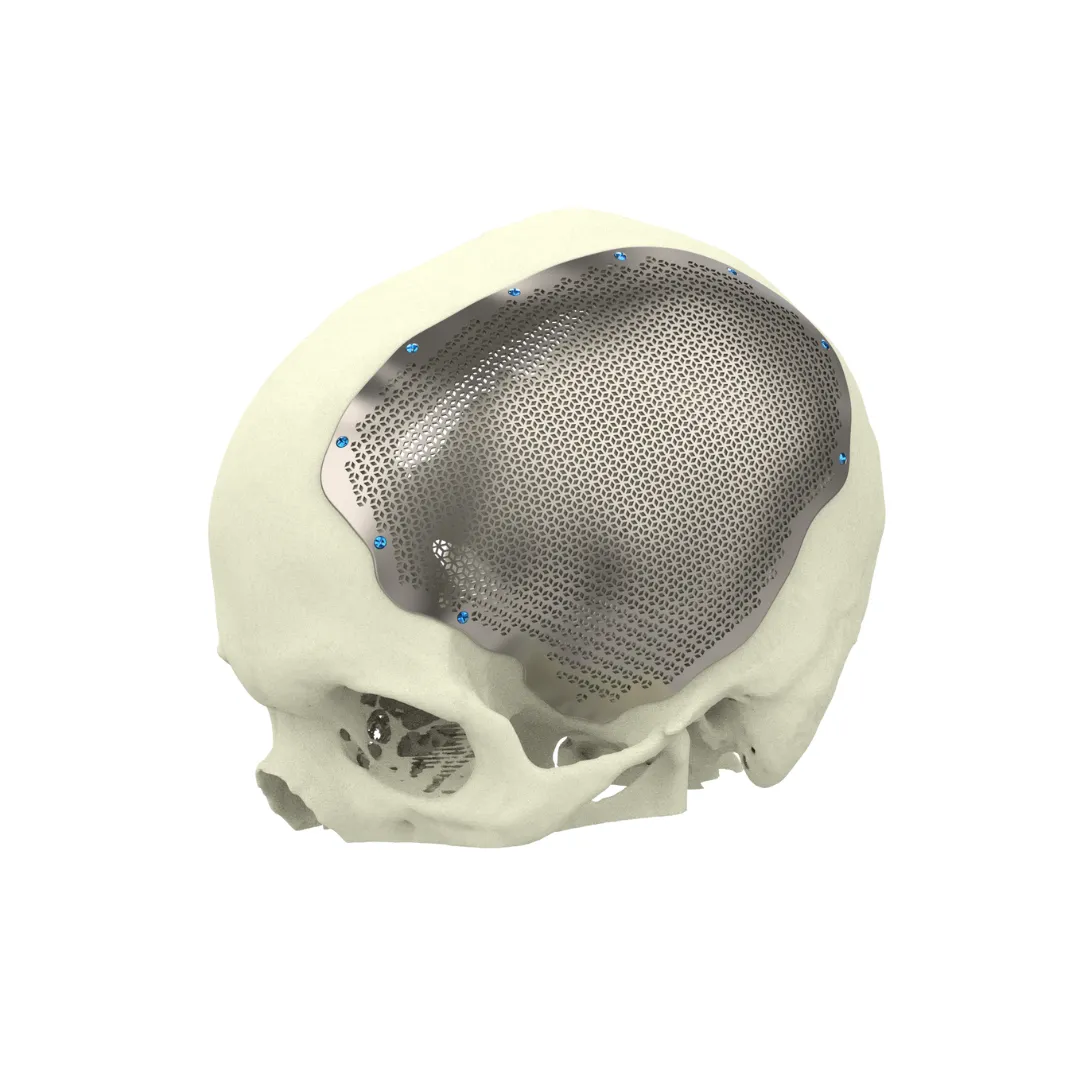

Microsurgery

Microsurgery

Median Nerve Release

Micro-decompression of the median nerve to treat Carpal Tunnel Syndrome, restoring hand function and eliminating numbness.